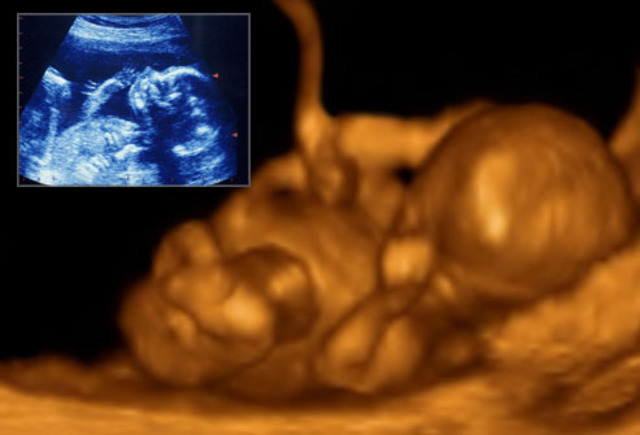

• Month 6 Baby

Month 6 Baby

About 8-10 inches (21-25 cm) long, about 8-12 ounces.

Fat deposits under skin, but fetus appears wrinkled.

Breathing movement begin.